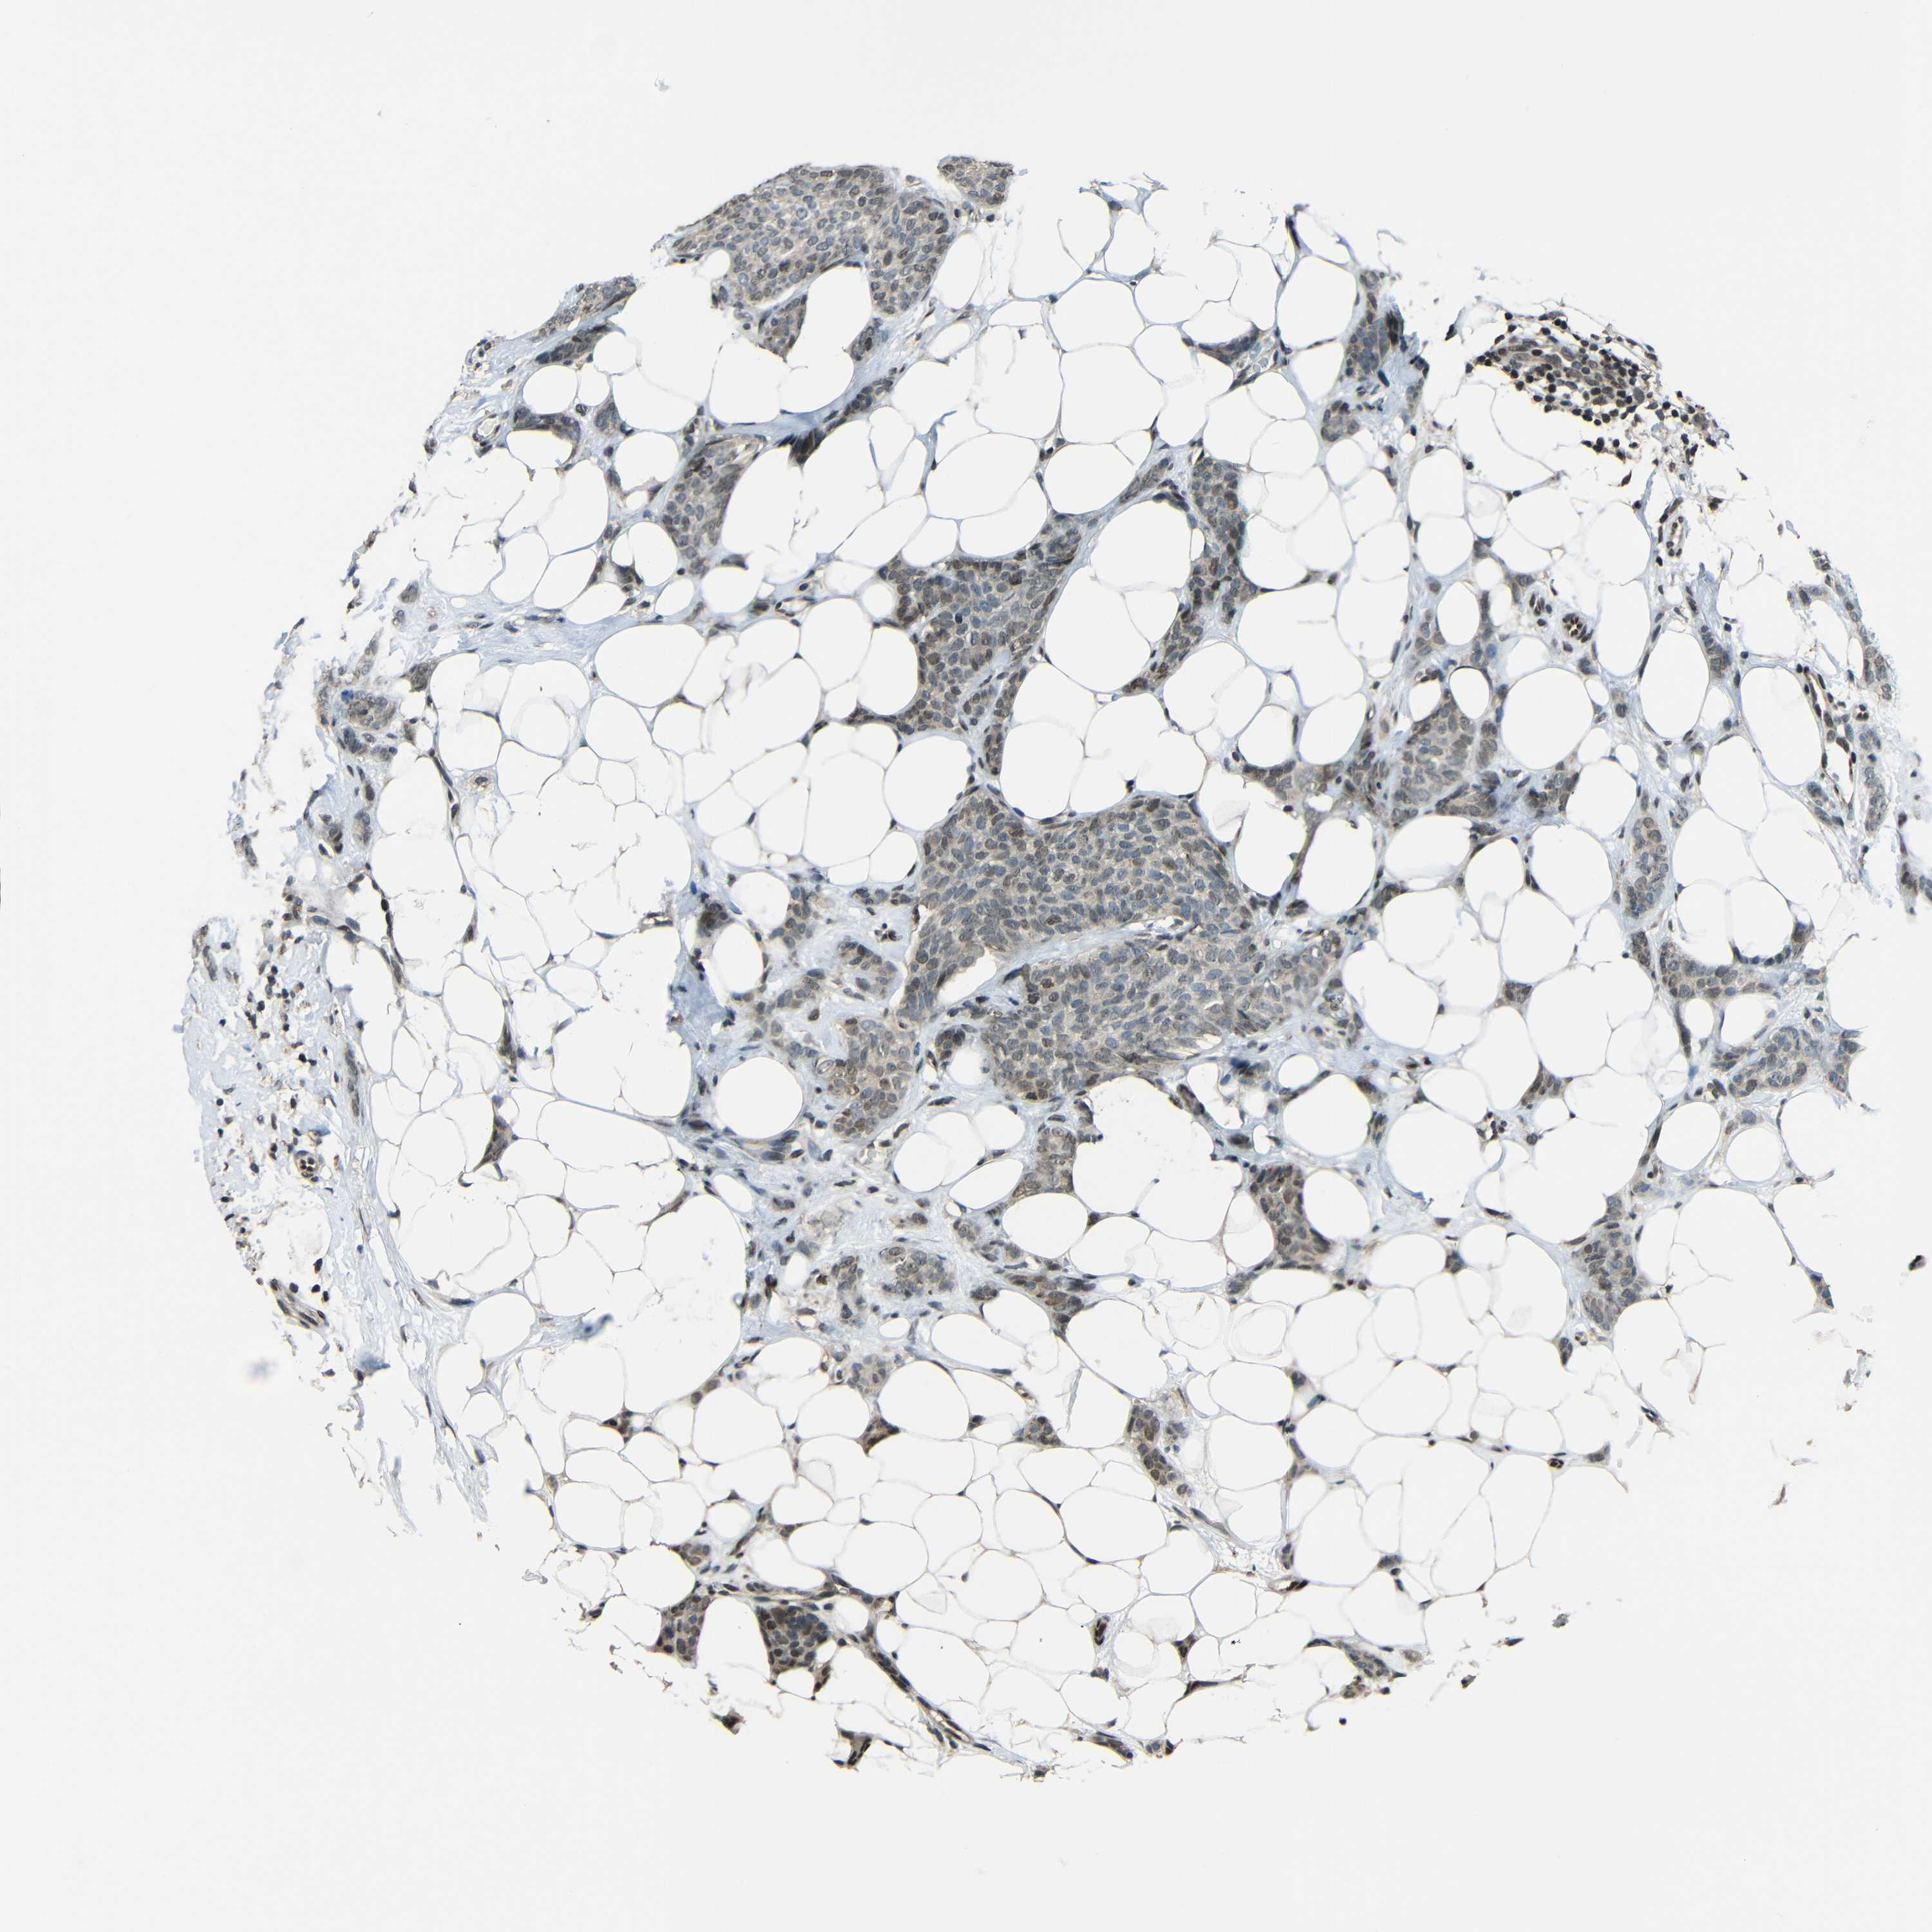

CANCER BREAST CANCER Show tissue menu

BRCA TCGA BRCA VALIDATION PROTEIN EXPRESSION